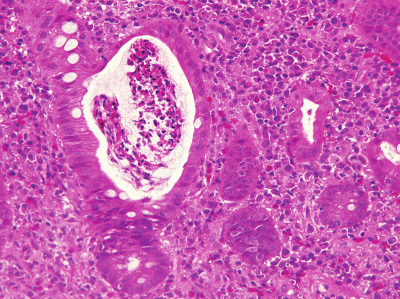

身長164cm、体重54kg。体温37.8℃。脈拍88/分、整。血圧120/60mmHg。眼瞼結膜は軽度貧血様である。内視鏡検査では結腸に多発性のびらんと潰瘍とを認める。採取された結腸粘膜生検組織のH-E染色標本を別に示す。

本標本に認められる所見はどれか。3つ選べ。